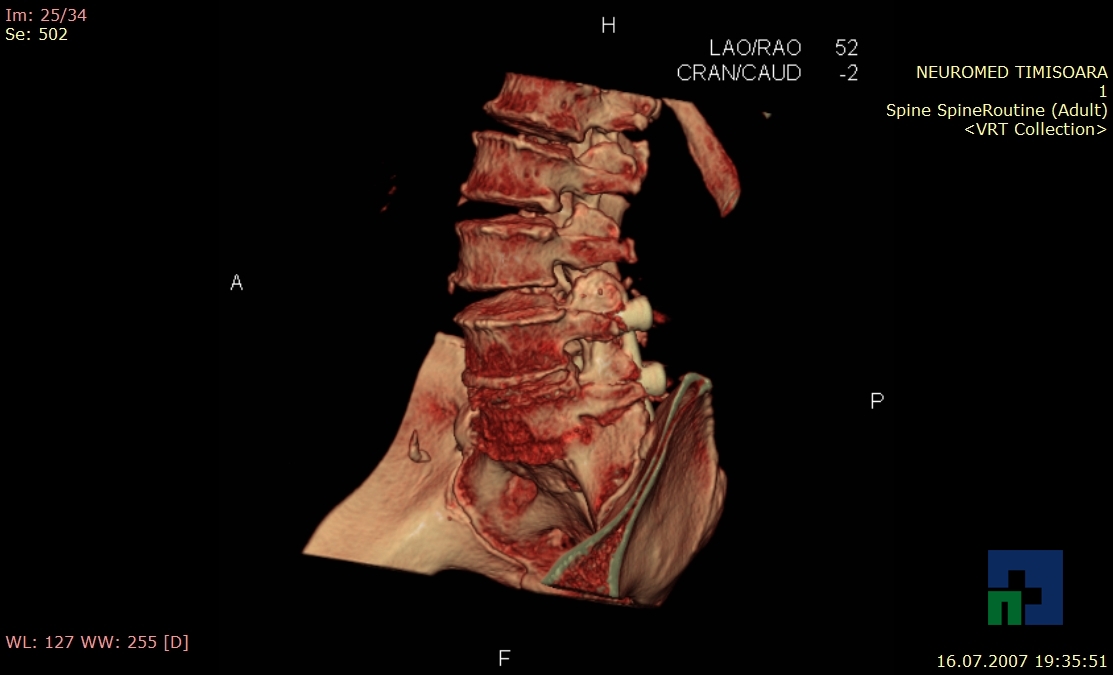

În cazul traumatismelor cranio-cerebrale:

- Diagnosticul edemului cerebral, a contuziei cerebrale, a leziunilor axonale difuze edematoase/hemoragice, a dilacerării cerebrale, a hematomului intraparenchimatos posttraumatic, a hematoamelor subdurale/extradurale (acute, subacute, cronice), a hemoragiei intraventriculare, a hemoragiei subarahnoidiene

- Diagnosticul traumatismelor de bază de craniu

- Diagnosticul fracturilor: